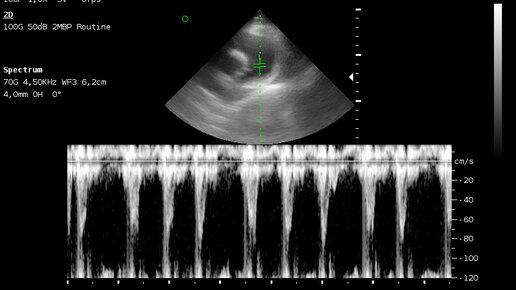

Чемпион международных и российских выставок, шпиц Яша, был на ЭХОкг сердца. Клиника БиоВет Новогиреево.

? ! Главная цель: выявить скрытые болезни сердца, чтобы кошка безопасно перенесла наркоз. 🔹 NT-proBNP (анализ крови) — быстрый скрининг - Это «маркер напряжения» сердца. ? Зачем: Простой анализ крови, который помогает заподозрить проблему, даже если у кошки нет симптомов. - Результат: Если уровень в норме — риск сердечных осложнений низкий. Если повышен — это сигнал, что нужно делать УЗИ сердца и менять план анестезии. 〰️〰️〰️〰️〰️〰️〰️〰️〰️〰️ 🔹 ЭхоКГ (УЗИ сердца) — точная диагностика - Это «золотой стандарт», который видит структуру сердца...